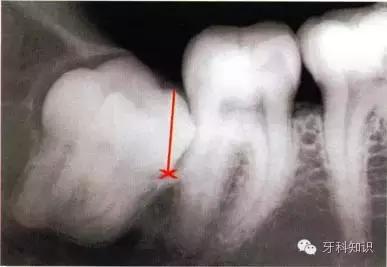

例一

a第Ⅱ类,b分类中位阻生。左下颌第三磨牙阻生,位于黏膜下。磨牙后区切开后,作近中切口,使用12号刀片沿牙龈扇贝状外形切透龈沟至牙槽嵴顶,避免将龈乳头切除。图中近中切口延长至第二前磨牙,便于翻瓣,更好地显露磨牙后区的骨质

a下颌第三磨牙阻生。代表牙槽窝深度的红线表明从牙槽嵴顶到釉牙骨质界间在近中颊角方向上的距离。考虑到患者的年龄,阻生牙牙槽窝的近中骨壁较容易以第二磨牙牙根旁的硬骨板为基础分化再生。因此,该患者第二磨牙牙槽骨修复重建的预后较好